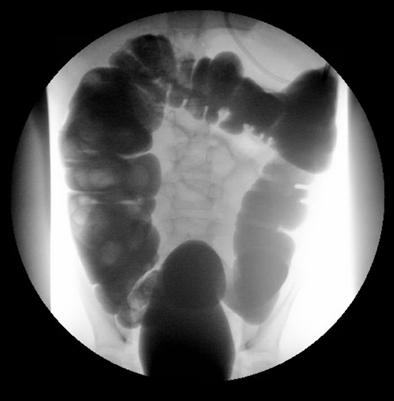

Exame com marcadores de Sitz: útil nos casos de constipação crônica ou refratária.[Figure caption and citation for the preceding image starts]: Exame com marcadores de Sitz com retenção dos marcadores ingeridos, na região retossigmoide de um paciente com constipaçãoDos acervos do Dr. R.A. Gomez-Suarez e Dr. J.E. Fortunato; usado com permissão [Citation ends].